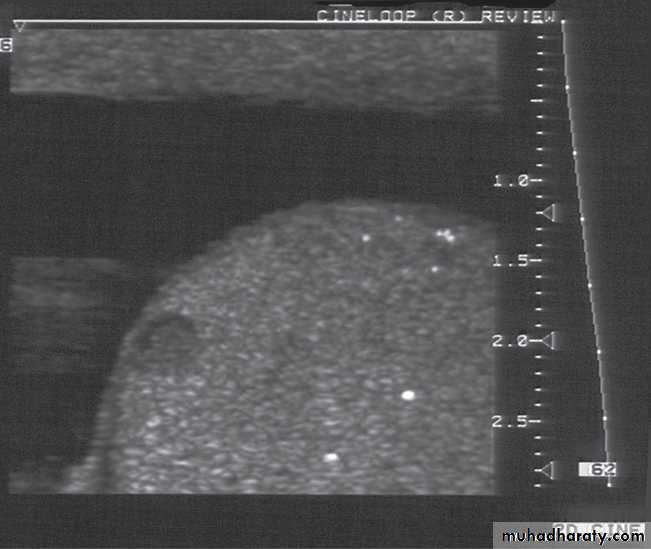

The scrotal contents are usually imaged with ultrasound, but MRI is occasionally used. The two main indications for scrotal ultrasound are 1.Scrotal swelling 2. Scrotal pain.In patients with scrotal swelling, it is essential to differentiate between an intratesticular cause, such as suspected testicular tumour, and an extratesticular cause, such as varicocele, hydrocele or infection (such as epididymitis or epididymo-orchitis) .

Doppler ultrasound can be used for patients with acute testicular pain and/or swelling to distinguish between testicular torsion, in which testicular perfusion is dramatically decreased, and acute epididymitis/orchitis, in which testicular perfusion is normal or increased.